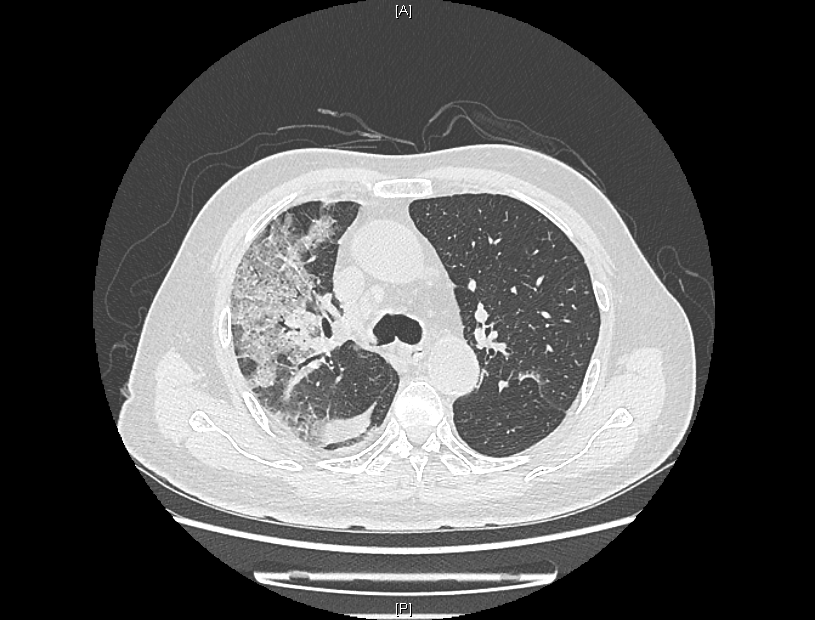

来院时,患者感染新冠病毒5天,持续发烧不退,出现了憋气、意识不清。患者入院后,经过医院持续监察发现,患者肺部CT逐步呈“白肺”状态,血气氧分压一度降至50mmHg,“正常血气氧分压为80-100mmHg,低于60mmHg,在临床上就可诊断为I型呼吸衰竭。”感染性疾病科主任林明贵说。

患者肺部CT检查图像

在多学科联合保驾之下,老人入院后5天病情出现了转机,成功解除无创呼吸机,并逐步从高流量吸氧降至经鼻导管吸氧。“当时看到肺部影像时,心已经凉了半截,做好了最坏的思想打算。”患者的儿子说,老人生病前爱好打乒乓球,希望此次康复后,重新回归他热爱的球场。